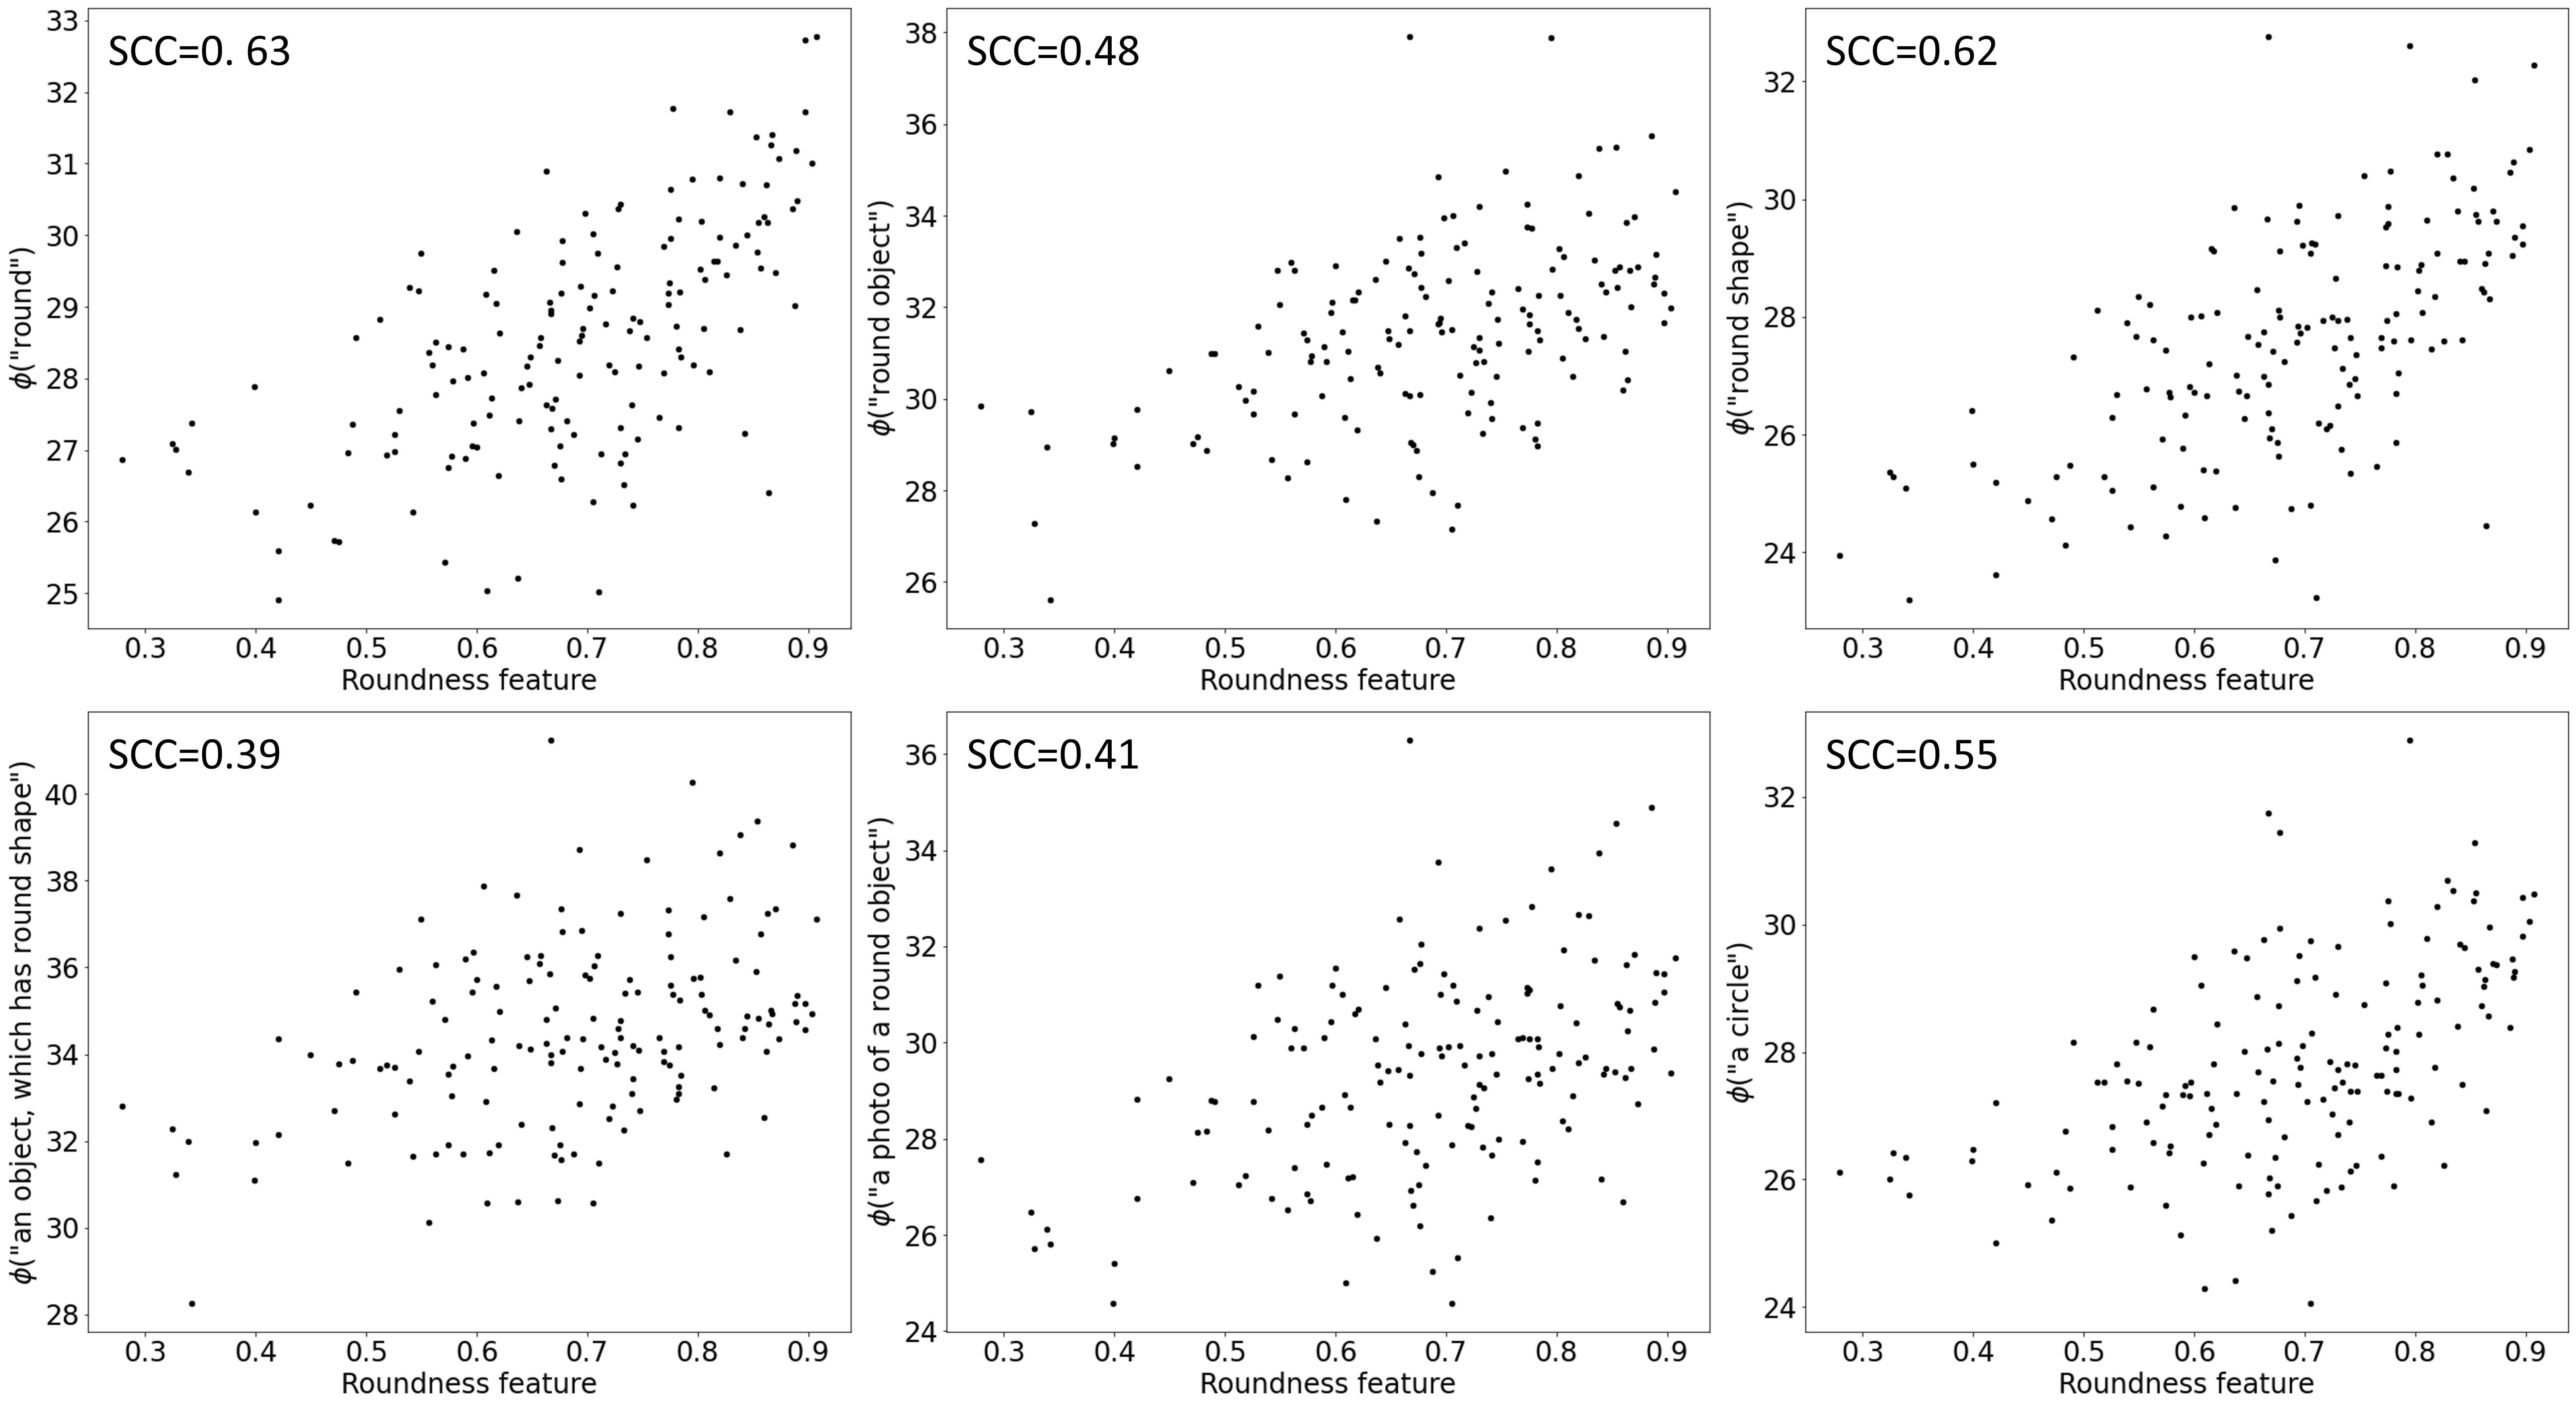

We examined how accurately the VLM can assess the shape of the breast masses. For this task, we used the segmentation masks to calculate the roundness and rectangularity features. Next, the computed shape features were compared with the outputs of the VLM obtained for the descriptors “round shape” and “rectangular shape”, respectively. Fig. 2 shows good correspondence obtained for the roundness parameter, with Spearman’s rank correlation coefficient (SCC) of 0.62. However, the model did not provide good results with respect to the rectangularity feature, SCC of -0.26. This result suggest that the capabilities of the VLMs to assess certain image features may be limited in practice. Additional results can be found in Appendix B, where we examined different roundness related text descriptors and concluded that simple descriptors (e.g. made of single words) are the most suitable for the shape assessment with VLMs.

Appendix 0.B Shape features and text descriptors

Additionally, we investigated how the phrasing of the roundness related text descriptor affects the relationship between the VLM output and the roundness feature calculated using segmentation mask. For this, we handcrafted the following six descriptors: “round”, “round object”, “round shape”, “an object, which has round shape”, “a photo of a round object” and “a circle”. Results presented in Fig. 5 shows that the better correlation coefficients were obtained for the most simple descriptors, with the “round” achieving the highest SCC of 0.63. The text descriptor crafting method suggested by Menon and Vondrick, which utilized full sentences, such as “a photo of a round object”, resulted in lower correlation coefficients compared to the basic plain descriptors [6].

Refer to caption

Figure 5: The relationships between the outputs of the VLM model for different roundness related text descriptors vs the roundness feature calculated based on breast mass segmentation masks. SCC stands for the Spearman’s correlation coefficient.